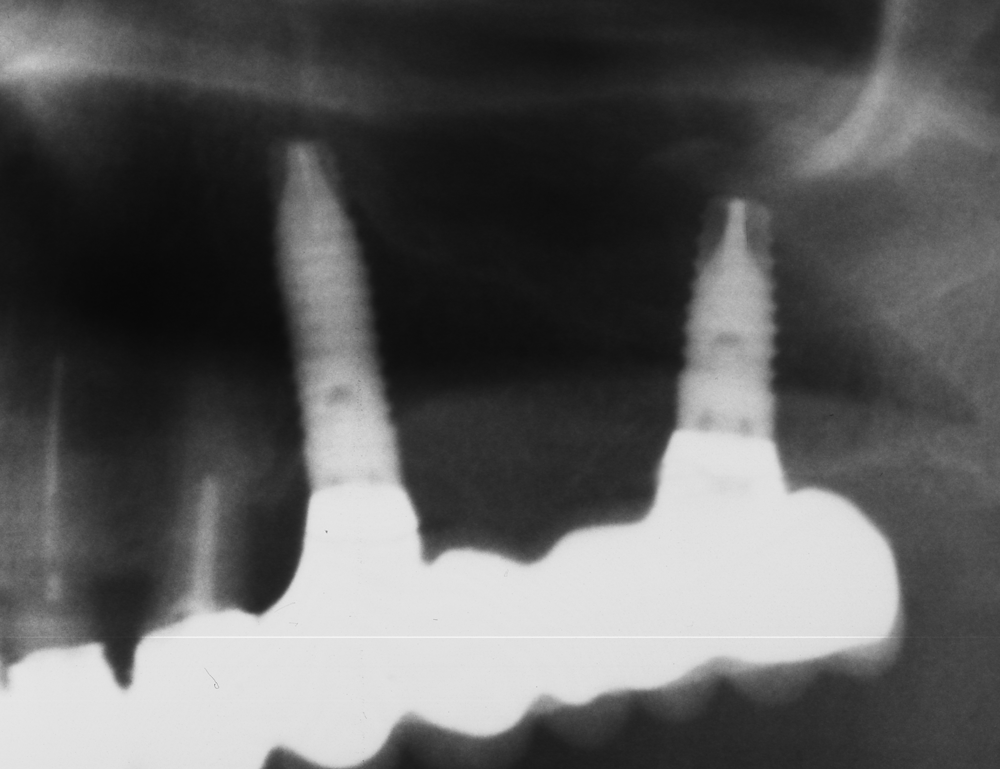

Случай на вертикален синуслифт със системата TBR - Франция, изработен през 2008 година